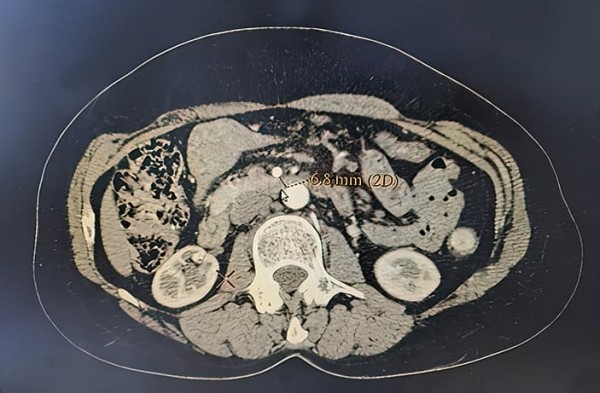

Диагностика. Были выполнены фиброгастродуоденоскопия с биопсией слизистой ДПК, МРТ органов брюшной полости, КТ органов брюшной полости с контрастированием (см. рис. 2 и 3), рентгеноскопия (см. рис. 1) и рентгенография желудка с двойным контрастированием, релаксационная дуоденография.

Рисунок 3. КТ ОБП с контрастированием (аксиальный срез).